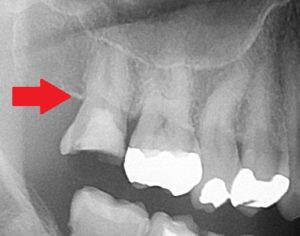

・右上7番目の歯

・前の歯医者で根管治療(歯の神経の治療)を行っていたが、痛みが強く、治らないため、某大学病院へ紹介された。大学病院では「歯を抜かないといけない」と言われた。その後、歯医者を探して当院に来院。

赤い矢印の歯です。